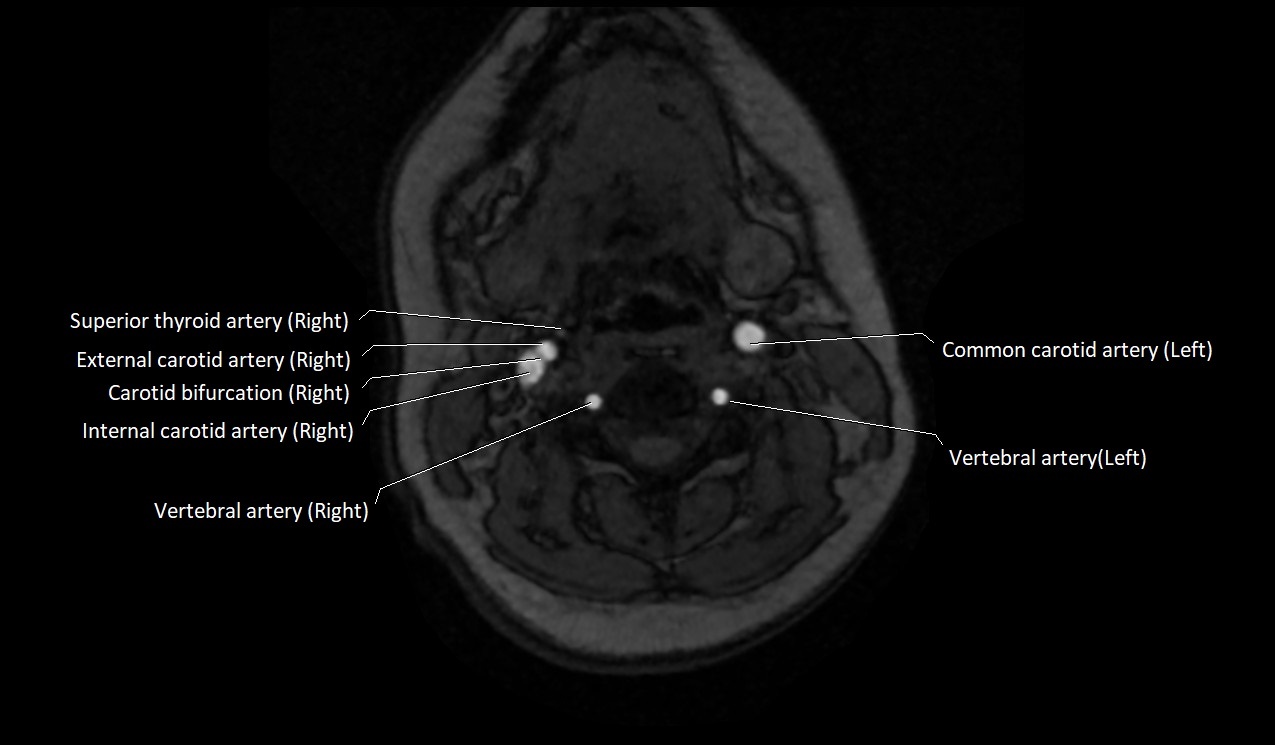

MRI Appearance:

• T1-Weighted Images:

• Appears as a tubular, hypointense (dark) structure relative to muscle

• May show flow void if the blood flow is fast

• T2-Weighted Images:

• Typically hypointense or isointense to muscle, but can be hyperintense if slow flow or stasis is present

MRI images

image